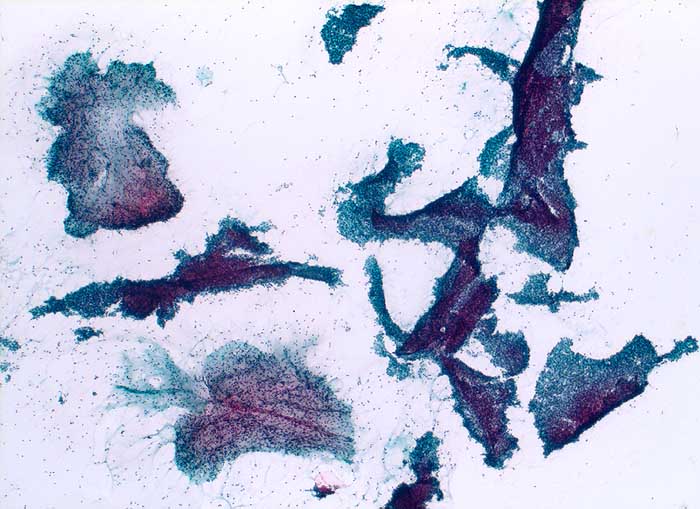

PathoPic – image database / PathoPic ID 5711 - Fibroadenom

Fibroadenom

benigner Tumor

Mamma

Feinnadelpunktion Mamma: Zahlreiche grosse, teils stark verzweigte und breite Verbände von regelrechten duktalen Epithelien. Im Ausstrichhintergrund zahlreiche bipolare nackte Kerne und immer wieder myxoides Stroma.

Histologische Diagnose: Fibroadenom mit ausgeprägtem Stromaödem

Zytologische Diagnose: Fibroadenom / phylloider Tumor

Zytologie

630